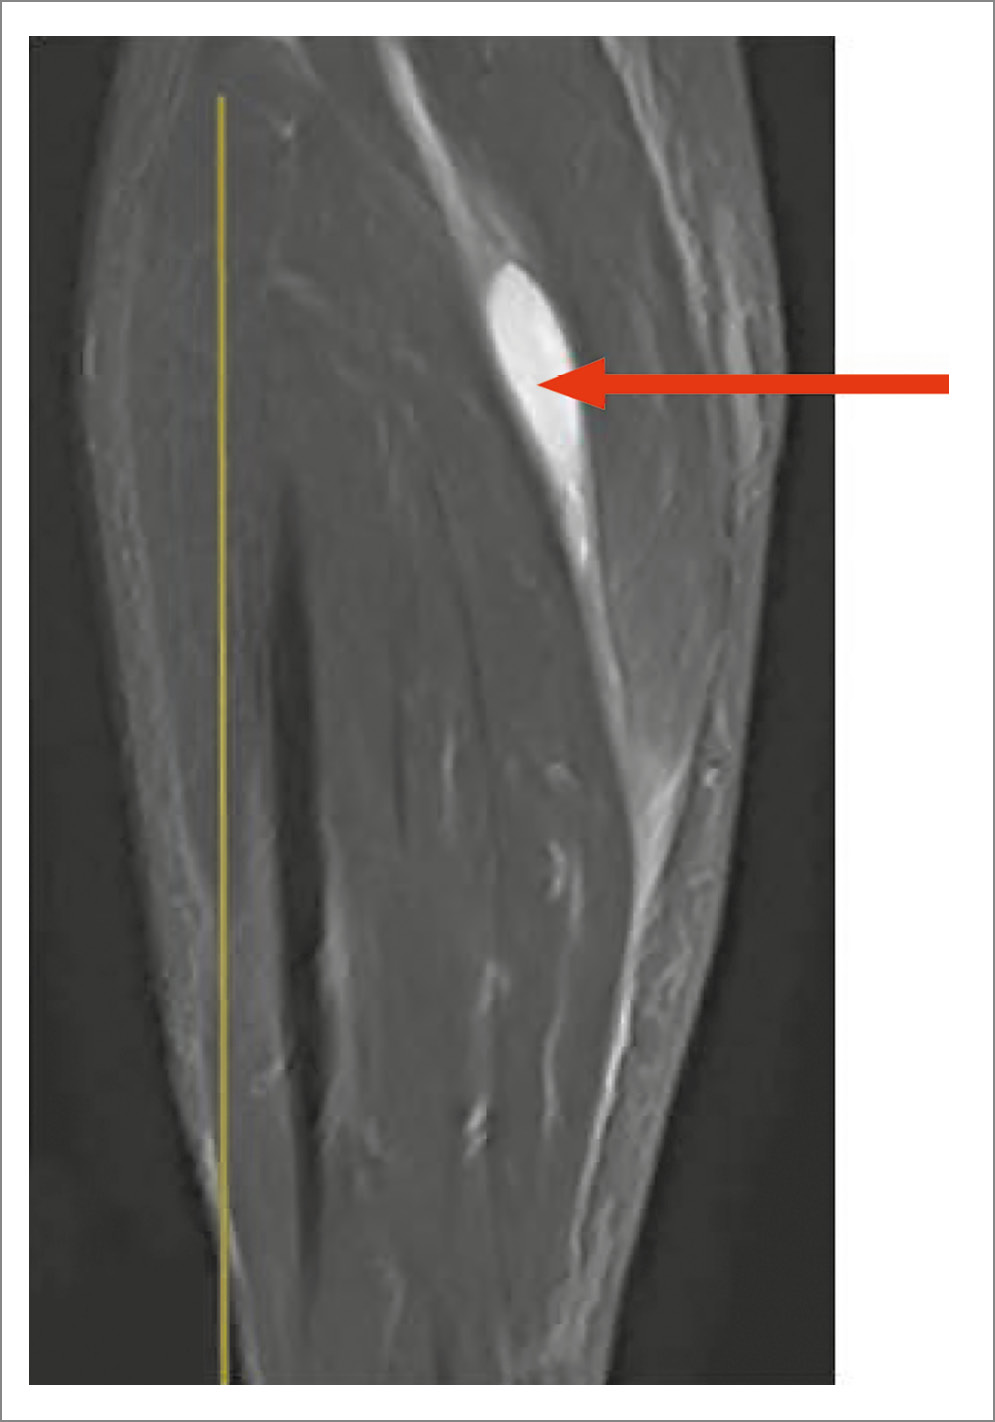

На МРТ разрыв КБ визуализируется как истечение жидкости в межмышечные пространства (рис. 3–5).

Рис. 5. МРТ голени, коронарный срез, Т2-ВИ STIR. Разрыв КБ, истечение жидкости в межмышечное пространство голени (красная стрелка).